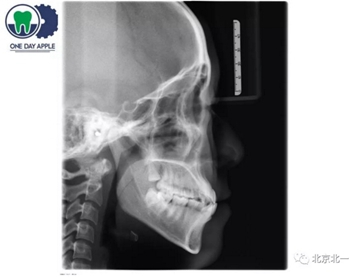

患者、男、40歲,下頜牙缺失數(shù)年來院咨詢種植。

檢查:46缺失, 47傾斜, 1度松動, 未見48萌出,

CBCT:骨量高度及寬度可, 48埋伏,低位阻生.37近中骨吸收

診斷:下頜牙列缺損, 48低位埋伏阻生 37 牙周炎

治療計劃:46種植, 同期拔除48 正畸扶正47.